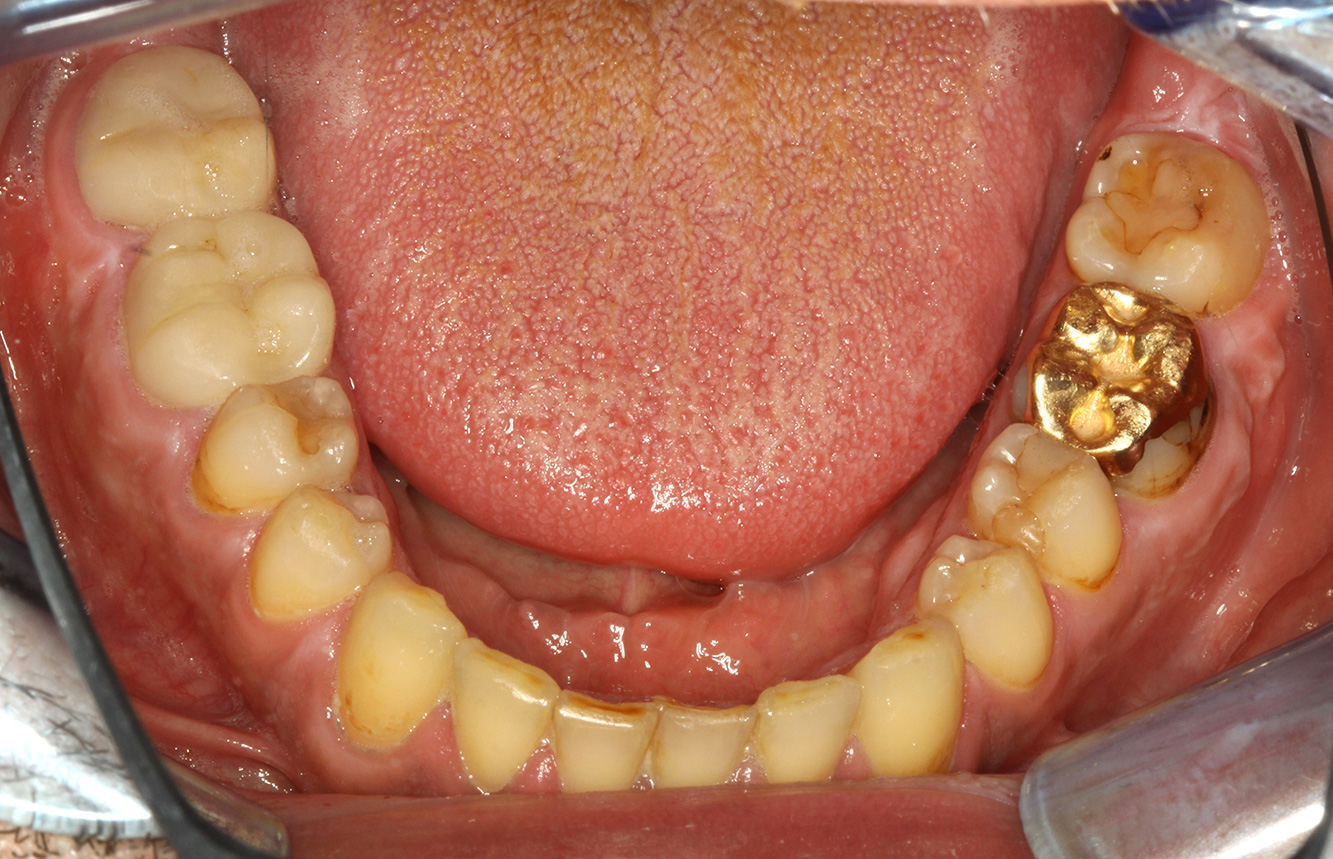

Il paziente ha 39 anni e in passato è stato sottoposto ad un intervento per la sostituzione della valvola aortica dovuta a insufficienza valvolare ed endocardite. Assume regolarmente l'ASS 100 come anticoagulante. Per quel che riguarda lo stile di vita, il regime alimentare seguito dal paziente è classificato come “dieta che favorisce la formazione della carie”, per via del consumo regolare di cibi ad alto contenuto di zuccheri e dei sei-sette pasti consumati al giorno. La salute orale del paziente indica un rischio moderato di carie, con lesioni attive. Il rischio di parodontite è basso, tuttavia il paziente è affetto da gengivite. Si formulano quindi i seguenti consigli per il trattamento di profilassi.

Per la seduta di profilassi non si possono formulare consigli per strumenti specifici. Si può ricorrere a un'applicazione mirata di air-polishing e lucidatura con testina rotante per rimuovere delicatamente placca e discromie lungo i margini del restauro e per ridurre le nicchie dove i batteri cariogeni possono formare nuove colonie (19).

Si consiglia una fluorizzazione per stimolare ulteriormente la prevenzione della carie, prevenire in particolar modo nuove formazioni intorno ai margini del restauro e per sigillare le superfici radicolari. Entrambi i provvedimenti possono ridurre la sensibilità dei denti alla temperatura.

A causa delle lesioni cariose attive e del rischio ad esse associato di progressione, si consiglia un intervallo di richiamo ravvicinato di tre-quattro mesi.